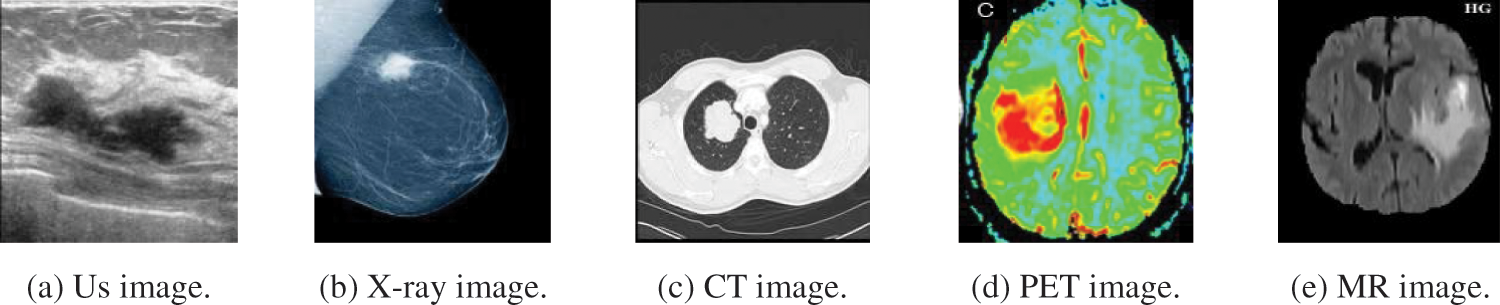

Fig. 2 illustrates a sample of the different modalities of medical images, (a) Us image, (b) X-ray image, (c) CT image, (d) PET image, and (e) MR image. Each of these images has two significant areas: background and tumor regions.

Figure 2: A sample of the different modalities of medical images